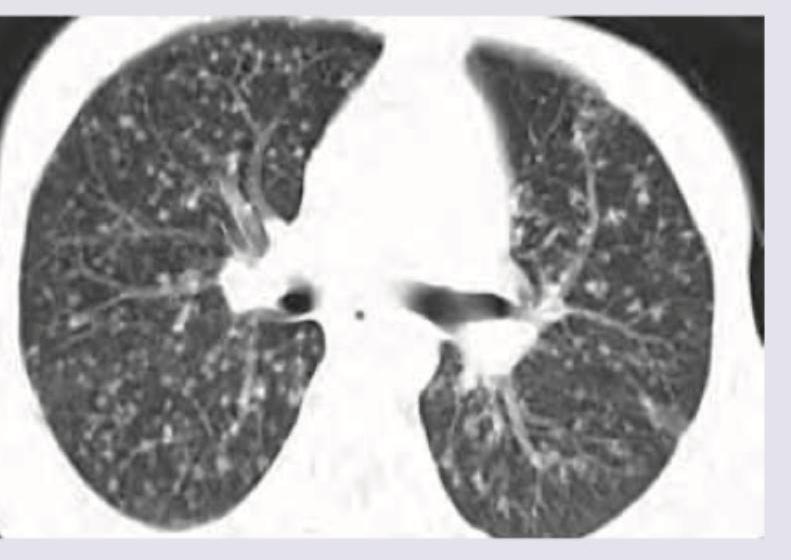

The following pattern in CT scan shown below can occur due to spread from:

Explanation: ***Pulmonary artery*** - The CT scan demonstrates a **miliary pattern** with numerous small (1-3mm), discrete nodules showing **random distribution** throughout both lungs - This random distribution is the hallmark of **hematogenous spread via the pulmonary arteries** - When pathogens or tumor cells reach the pulmonary arteries (from right heart or systemic venous circulation), they disseminate uniformly throughout lung parenchyma - Classic examples include **miliary tuberculosis** and **hematogenous metastases** (thyroid, renal, melanoma) *Lymphatics* - Lymphatic spread produces a **perilymphatic distribution**, NOT a miliary/random pattern - Nodules appear along lymphatic pathways: peribronchovascular bundles, interlobular septa, and subpleural regions - Creates a characteristic beaded or nodular appearance along lymphatic routes - Seen in **sarcoidosis** and **lymphangitic carcinomatosis**, which do NOT present with miliary patterns *Bronchial vein* - Bronchial veins drain deoxygenated blood from bronchial walls to the systemic circulation (azygos/hemiazygos system) - This is NOT a recognized pathway for producing miliary lung nodules in standard radiology literature - Miliary patterns specifically refer to pulmonary arterial hematogenous dissemination *All of the above* - Incorrect: The miliary pattern is specifically caused by **pulmonary artery spread only** - The random distribution seen in the image is pathognomonic for hematogenous spread via pulmonary arteries, not lymphatic or bronchial venous routes